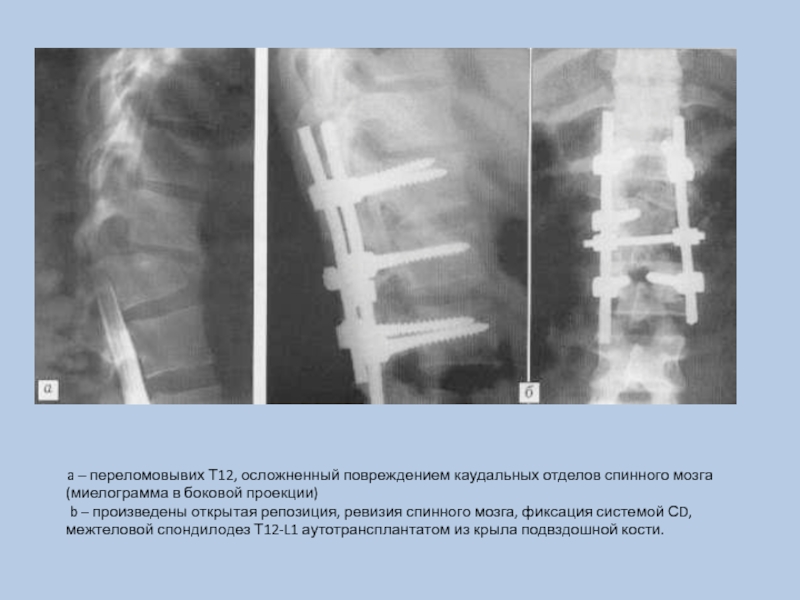

Слайд 12 a – переломовывих Т12, осложненный

повреждением каудальных отделов спинного мозга (миелограмма в боковой проекции) b

– произведены открытая репозиция, ревизия спинного мозга, фиксация системой СD, межтеловой спондилодез Т12-L1 аутотрансплантатом из крыла подвздошной кости.

a – переломовывих Т12, осложненный повреждением каудальных отделов спинного мозга (миелограмма в